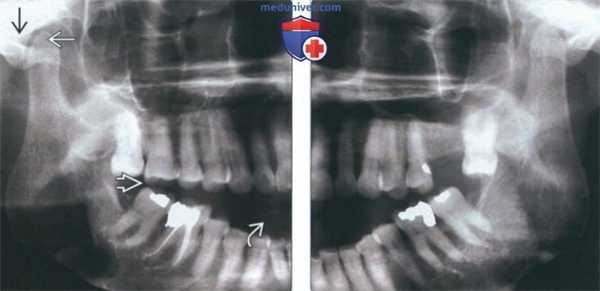

При сочетанной травме проводят панорамную томографию зубных рядов (ортопантомографию), однако при изолированном поражении одного или нескольких зубов фронтального отдела данный метод исследования следует считать неинформативным.

(Слева) На фотографии виден вывих центрального резца верхней челюсти слева в сторону губы (вариант бокового вывиха).

(Справа) На периапикальной рентгенограмме у этого же пациента не определяются изменения в этой плоскости, поскольку зуб смещен в сторону губы. На КЛКТ (исследование в этом случае не было доступно) может обнаруживаться расширение пространства периодонтальной связки (НДС) со стороны губы. Была выполнена ручная репозиция зуба и шинирование. (Слева) На периапикальной рентгенограмме у этого же пациента через десять лет после травмы определяется, что вершина корня зуба закрыта; вмешательство на каналах не требуется. Пульпа пораженного зуба обызвествлена, скорее всего, в от вет на травму.

(Справа) На периапикальной рентгенограмме определяется вколачивание и перелом резцового края центрального и бокового резцов слева. Обратите внимание на отсутствие пространства ПДС в области вершины корня центрального резца. (Слева) На периапикальной рентгенограмме состояние после репозиционирования и стабилизации вколоченных центрального и бокового резцов проволокой и композитной шиной. Обратите внимание на признаки рарефицирующего остеита рядом с вершиной корня бокового резца.

(Справа) На контрольной периапикальной рентгенограмме у этого же пациента определяется внутренняя и наружная резорбция зубов, т.к. лечение корневых каналов было начато, но не завершено.